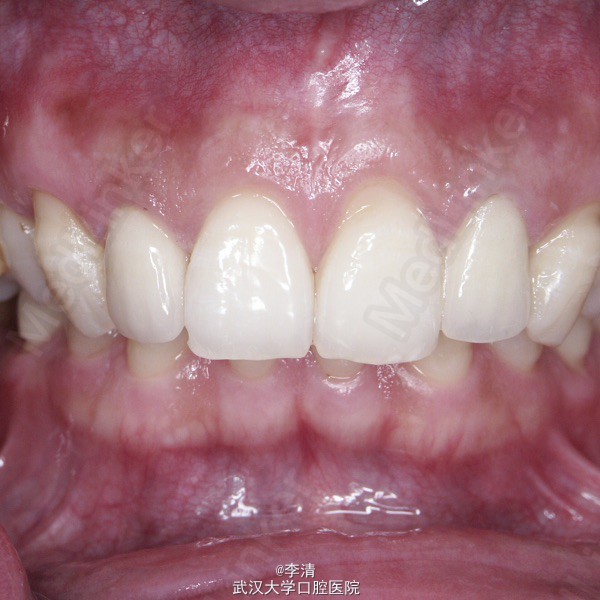

随访 讨论

患者对修复的美观效果满意。术后无牙龈炎症。